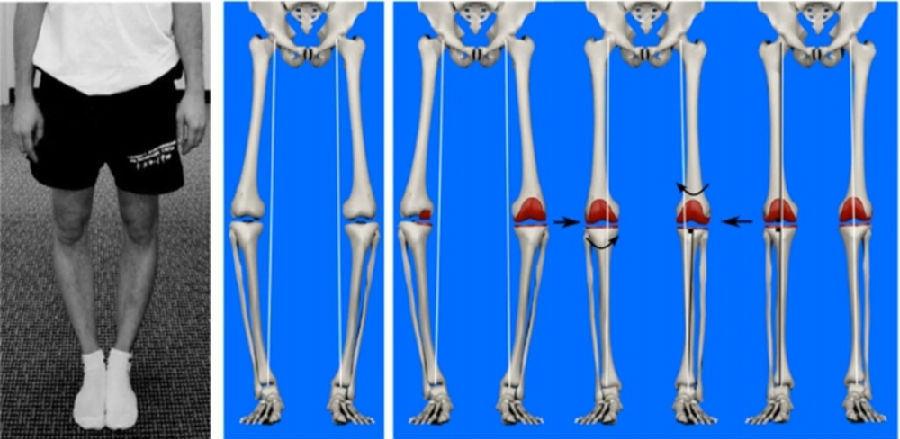

数十年来,机械轴对线(MA)一直被作为TKA精准对线的金标准,通过分别垂直于胫骨和股骨机械轴截骨,构建符合生物力学的人工膝关节。MA-TKA具有良好的假体长期生存率,但仍有10%~20%的患者对疗效不满意,原因在于MA-TKA改变了膝关节的旋转中心、关节线倾角、原始力线和髌骨对应关系等。因此,为追求更优的膝关节运动学和功能结果,有学者提出了其他对线技术。

②运动学对线(KA),基于患者个性化的股骨屈曲轴、胫骨平台旋转轴和髌骨屈曲轴三轴定位,实现完全解剖位置的TKA假体植入,恢复患者自然的下肢力线;

③限制性运动学对线(rKA),遵循KA的主要技术原则,保留股骨侧假体的运动轴对线,通过微调胫骨侧假体的位置来调整下肢力线和关节面倾斜度;

研究表明这些TKA对线技术的应用能够取得良好的临床疗效,但是应用于严重畸形病例仍具有一定的局限性。原因在于aMA、rKA、AA和FA这四类对线技术的目标下肢力线范围在0°±3°内,仅通过截骨矫正畸形程度有限,仍需适当松解软组织以恢复屈伸间隙的平衡。此外,KA对线技术仅通过截骨进行解剖重建,术后残留畸形度数往往超出0°±3°范围,而目前下肢力线的安全范围尚无绝对统一标准。